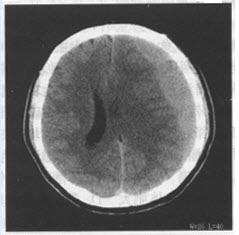

患者男,24岁。头部被球击中,1周后出现持续性头痛、头晕,结合CT图像,最可能的诊断是()

A:硬膜外血肿

B:脑挫裂伤

C:急性硬膜下血肿

D:亚急性硬膜下血肿

E:慢性硬膜下血肿